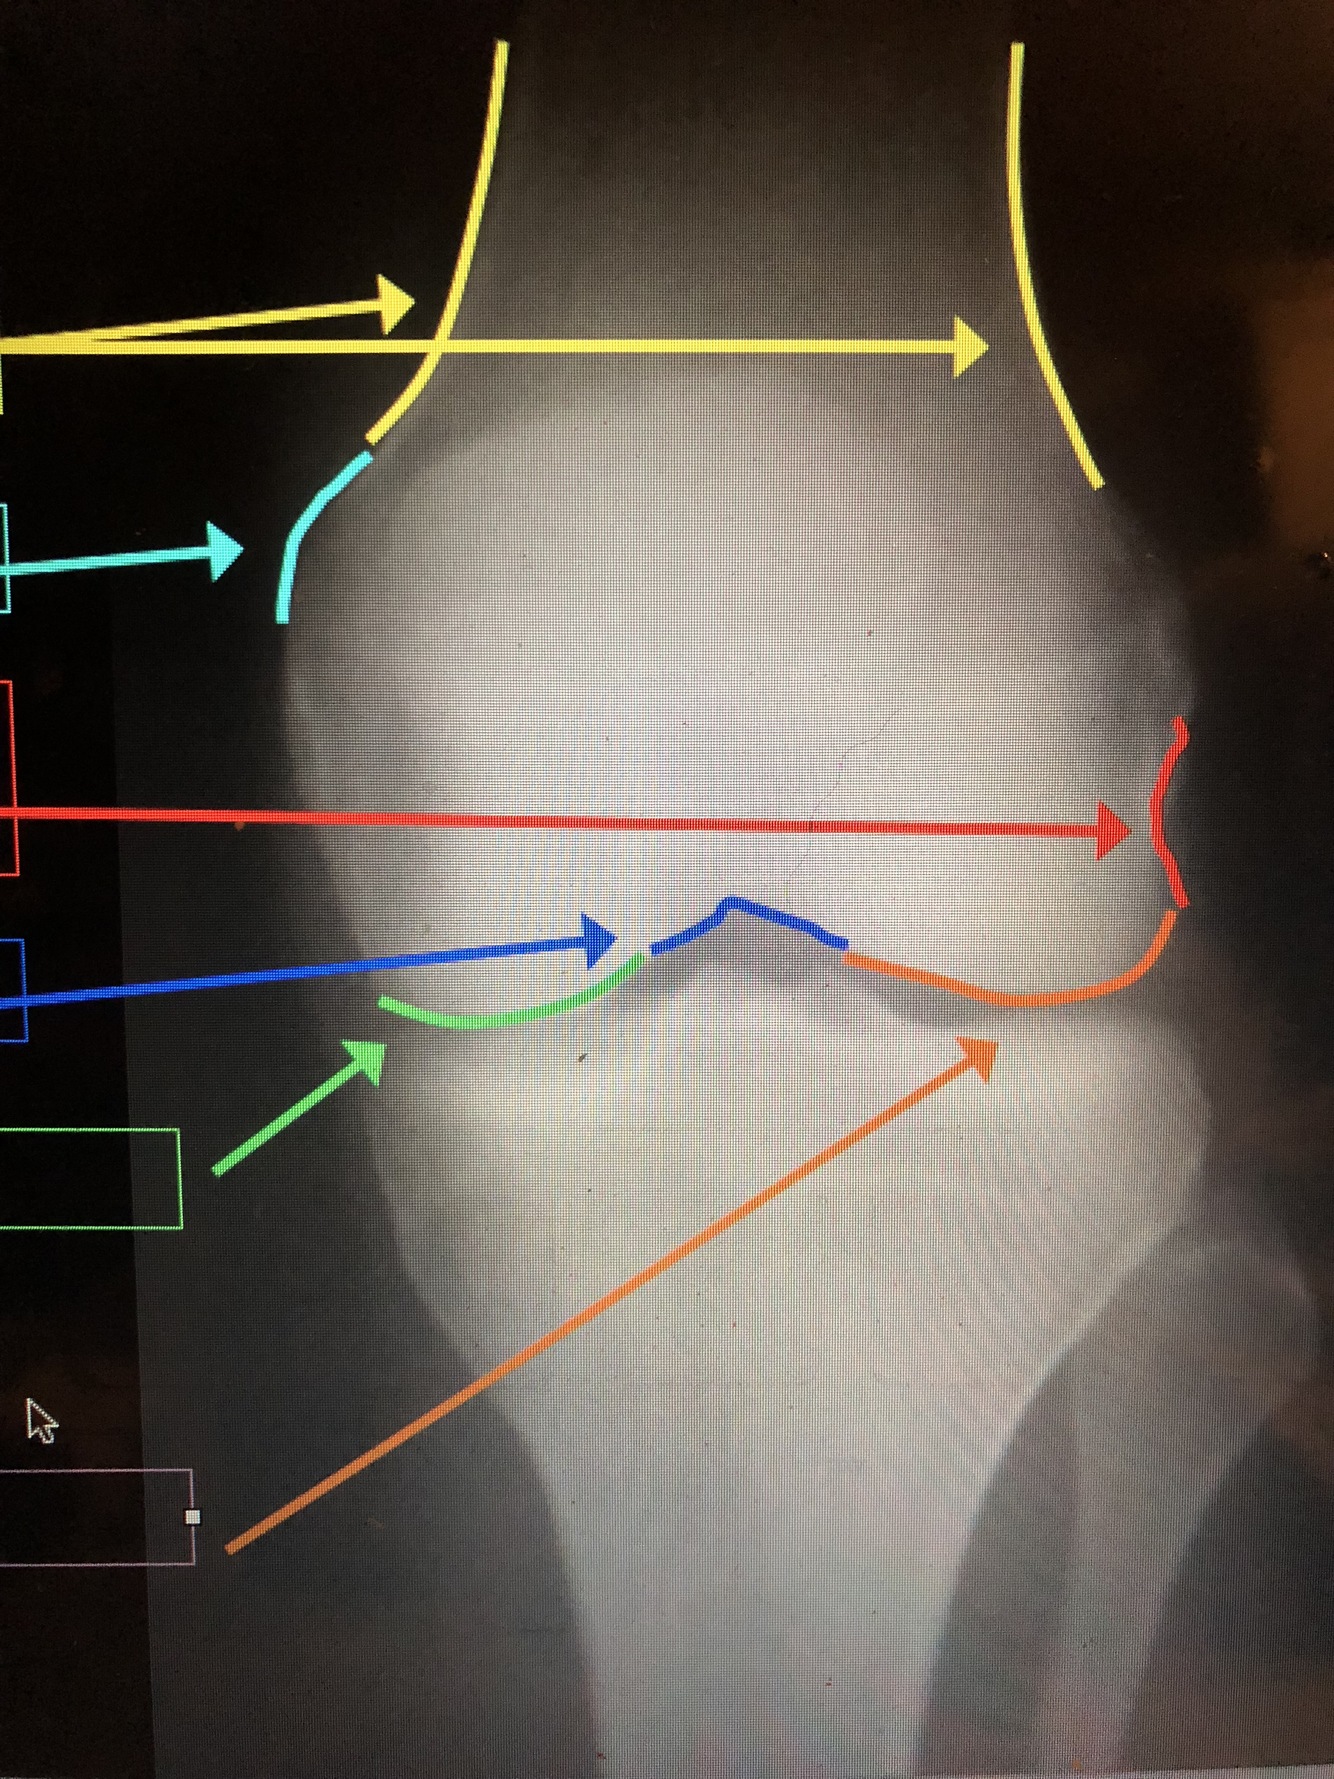

What is the yellow line?

Medial Femoral Condyle

•Usually is larger and is projected more distally

What is the dark blue lines?

Epicondyles (med. & lat.)

what is the light blue lines?

Femoral Condyles (med. & lat.)

What is the light blue line?

Adductor Tubercle

What is the dark blue line?

Intercondylar Notch

What is the green line?

What is the orange line?

Lateral Femoral Condyle